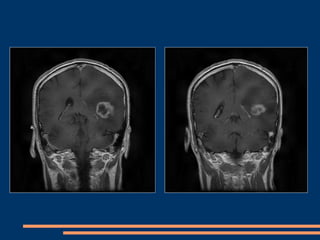

CAS CLINIQUES –GIESSEN+CHU FORT de FRANCE Patient de  35  ans  (GIESSEN) Ralentissement  psychomoteur depuis 1 mois , déficit moteur de l’hémicorps droit d’installation progressive , aphasie  de Wernicke et Broca. Juin 2009 : réalisation d’une IRM cérébrale montrant un glioblastome temporal profond gauche avec effet  de masse. Opéré avec GLIOLAN couplé au Pentero avec option fluoroscopie.

IRM pré-opératoire

IRM pré-opératoire (suite)